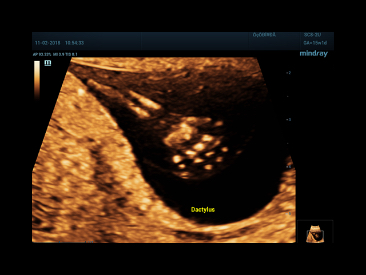

Since the company was founded, Mindray is continuously exploring new ways to improve diagnostic confidence. Powered by the most revolutionary ZONE Sonography? Technology, the ZST+ platform brings ultrasound image quality to a higher level by zone acquisition and channel data processing.

Thanks to the innovative, software-driven ZST+ platform, the Resona series is continuously evolving with the leading-edge technologies to meet the most challenging diagnostic demands in womenŌĆÖs health practice. More importantly, it is designed with the understanding that the wisdom of experts is always precious, and you need more intelligent partner for enhanced speed and confidence. Finally, Resona series with Zone Intelligence provides a total solution to help you with diagnostic confidence, efficiency, and standardization across different diagnostic challenges in todayŌĆÖs demanding and overburden hospital environment.